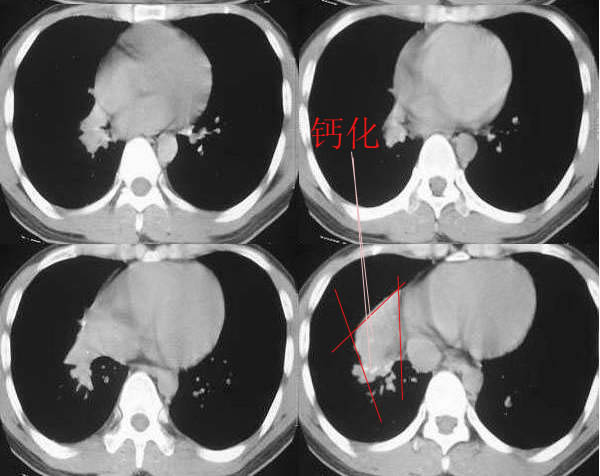

男,28岁,右胸不适,轻咳.余无特殊症状.请各位大侠发表见解

右肺下叶背段结核灶!肺门下方病灶没有传完整,不好说!看其形态,感觉象肺段实变,而且里面有散在点状钙化,不象是占位性病变.

28岁,右肺下叶背段病变,未见实质肿块,病灶内见钙化,及卫星灶,纵隔内有肿大淋巴结,结核吧,不象占位病变

右肺下叶背段结核灶,肺门软组织肿快影伴点壮钙化,考虑结核。纵隔淋巴结肿大。

右肺门区软组织肿块,边缘钙化,右肺中叶不张,右下叶背段结节状及斑片状影。首先考虑结核,建议支气管镜检查排除其他。

右侧中间段支气管管壁增厚,管腔狭窄,形成块状软组织密度灶,右肺中叶膨胀不全,右肺下叶背段斑块状、片状阴影,且伴钙化,考虑:右侧中间段支气管内膜结核伴中叶不张、右肺下叶背段结核

右下叶背段及下叶内后基底段见斑点状及小片状影,有钙化。右下所谓的软组织密度影不在肺门,而是在下肺静脉层面以下,与膈相近,可能是横膈部分图像,图像没传完,易误导大家。综合考虑感染性病变(结核可能性大)